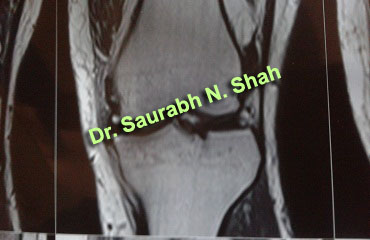

ACL

Case 1

Case 2

Case 3